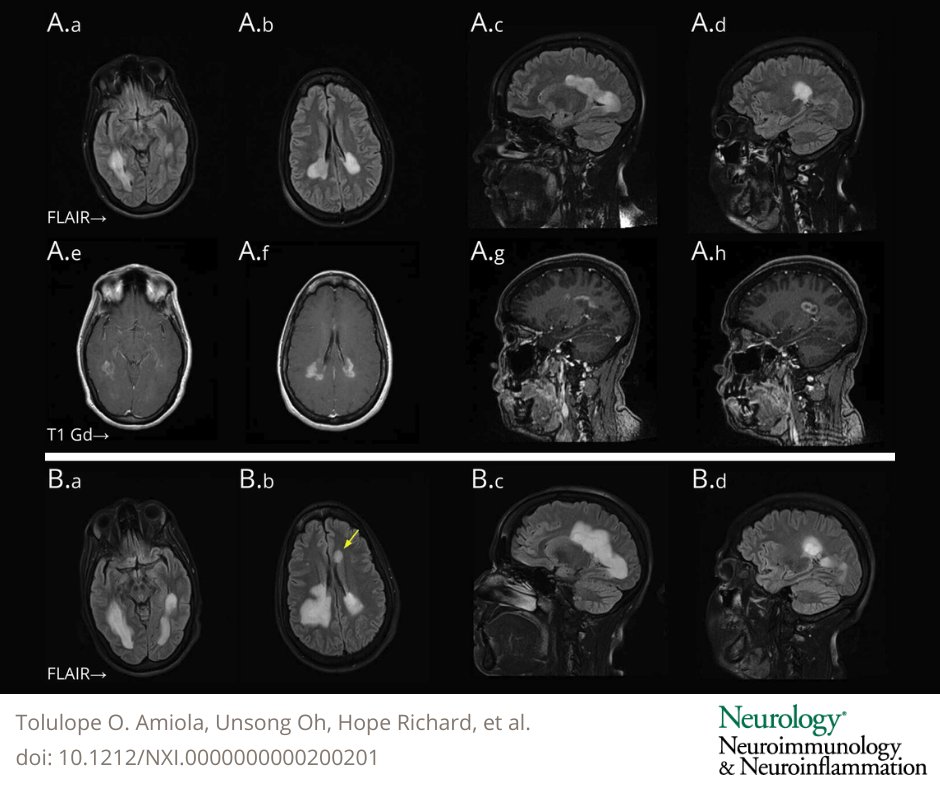

Diagnostic & Treatment Challenges: A 42-Year-Old Woman With Rapidly Expanding White Matter Lesions—From the National Multiple Sclerosis Society Case Conference Proceedings bit.ly/3OpIyUN #MS #NeuroTwitter

Diagnostic &amp; Treatment Challenges: A 42-Year-Old Woman With Rapidly Expanding White Matter Lesions—From the National Multiple Sclerosis Society Case Conference Proceedings bit.ly/3OpIyUN

#MS #NeuroTwitter